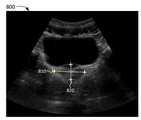

도 8은 여기서 기술된 구현예에 따른 전립선 크기를 결정하는 것을 보여주는 다이어그램 800이다. 도 8에 도시된 바와 같이, 다이어그램 8000은 환자 전립선의 초음파 영상을 포함하고, 여기서, 전립선의 크기는 전립선 ML 모델 560에 의하여 수행되는 분할에 기초한 서로 다른 2개의 차원에서 결정된다. 예를 들어, 전립선 ML 모델 560은 초음파 영상이 캡쳐된 특정 평면에서 전립선의 폭 810 및 전립선의 높이 820를 결정할 수 있다.8 is a diagram 800 illustrating determining prostate size in accordance with embodiments described herein. As shown in FIG. 8 , diagram 8000 includes an ultrasound image of a patient's prostate, where the size of the prostate is determined in two different dimensions based on segmentation performed by the